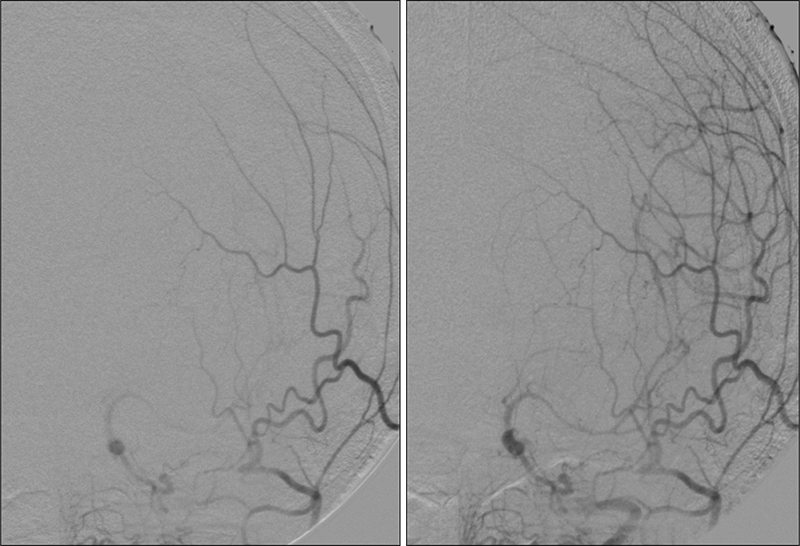

Εικόνα 10: Τοποθέτηση του εγγύς συστήματος προστασίας MOMA με διάταση του περιφερικού μπαλονιού στην αρχή της αριστερής έσω καρωτίδος.

Εικόνα 11: Αποκατάσταση της στενώσεως του αριστερού καρωτιδικού βολβού με  τοποθέτηση stent τύπου closed-cell.

Εικόνα 12 και 13: Κατά την ενδοκράνια προσθιοπίσθια και πλάγια προβολή της αριστερής κοινής καρωτίδος μετά την επέμβαση, παρατηρείται σημαντική αιμοδυναμική βελτίωση με αναστροφή της ροής στην αριστερή πρόσθια εγκεφαλική αρτηρία που είναι πλέον ομόδρομη.